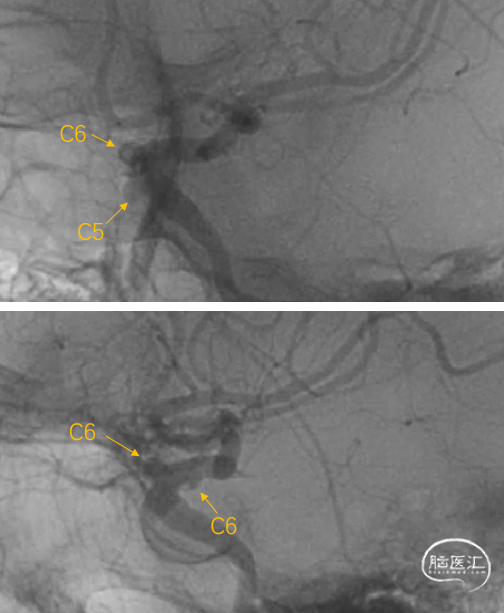

左侧颈内动脉多发动脉瘤

1:C6段,大小约2.9mm×2.0mm×1.3mm、瘤颈宽2.9mm;

2:C6段,大小约3.6mm×3.5mm×2.2mm、瘤颈宽2.9mm;

3:C5段:大小约3.5mm×3.3mm×2.4mm,瘤颈宽5.0mm;

经Fastrack微导管输送FD到位

缓慢回撤Fastrack微导管,FD头端在颈内动脉末端V形打开,确认FD远端锚定点位于A1分叉近端

继续缓慢回拉释放支架

虹吸弯处适当推拉,使支架贴壁良好

支架完全完全打开,完全覆盖全部动脉瘤